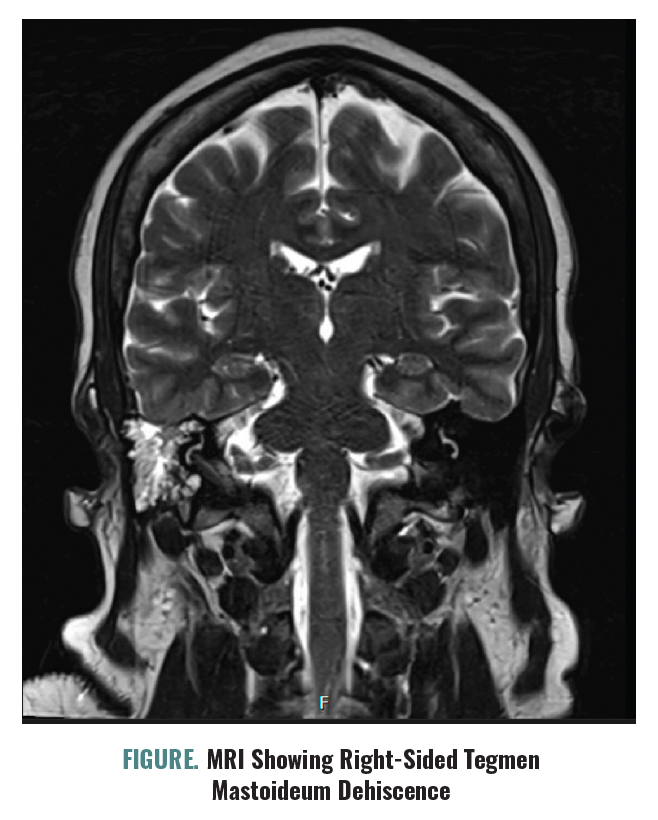

Dr Smith self-reports that she believes her change in mental status is due to issues with her pituitary gland, explaining that during the past 3 months she has experienced right-sided ear fullness, clear rhinorrhea, and pulsatile tinnitus. She notes increased rhinorrhea after a stressful argument, prompting outside hospital evaluation. She met with an ear, nose, and throat doctor (ENT) who confirmed the presence of a right-sided tegmen mastoideum dehiscence and CSF leak, which was evaluated with a lab assay. Surgical correction had been discussed but not scheduled.

FIGURE. MRI Showing Right-Sided Tegmen Mastoideum Dehiscence

An MRI (Figure) reconfirms the presence of a right-sided tegmen mastoideum dehiscence. Consultation with ENT and neurosurgery determines that changes in mental status are unlikely to be caused by the CSF leak. A lumbar puncture is performed and reveals a slightly above-normal opening pressure (25 mm Hg), which is notable given the presence of an ongoing leak. Dr Smith consents to a trial of acetazolamide 250 mg daily.